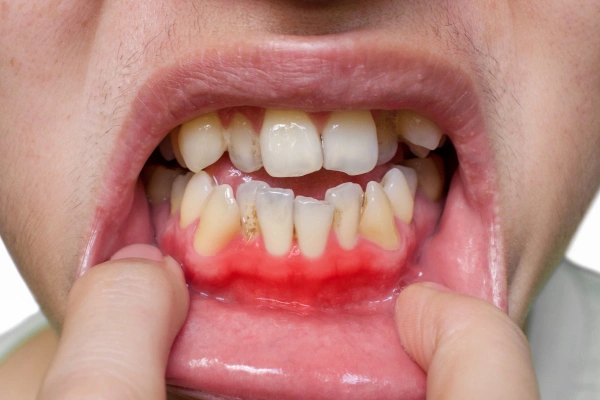

Recurrent gum infections around a partially erupted tooth

Indicates insufficient space for proper cleaning.

• Preventing gum inflammation around partially-covered teeth